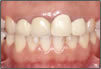

【審美歯科治療】

白い物(セラミック)を用いているだけが審美歯科治療ではありません。審美歯科治療とは歯周組織が健康で機能的にも問題がなく、見た目においても調和がとれ、長期的に安定した治療のことをいいます。

症例1審美歯科治療前症例2審美歯科治療後

▲症例1 治療前▲症例1 治療後